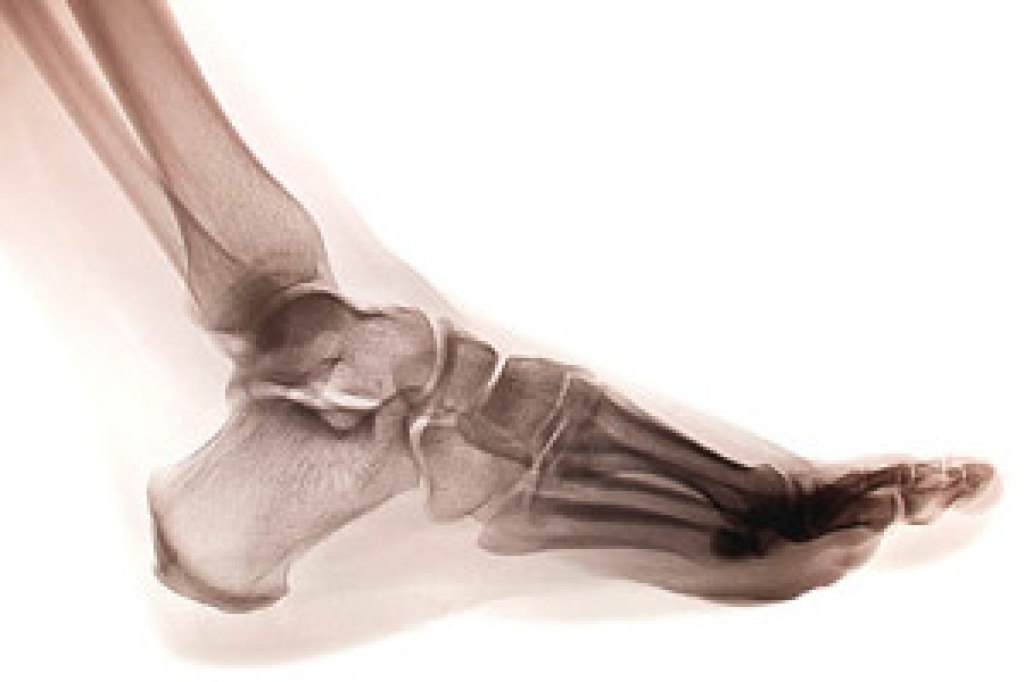

There are several bones in each foot, and a stress fracture occurs when there is a hairline break in one of the small bones. It often happens as a result of repetitive stress the feet endure from running or from frequently participating in jumping activities. The fractures are typically very small, despite how painful they can be. Many people choose to ignore the nagging pain in their foot, and it often becomes worse if it is not promptly treated. It may be a common injury among runners who increase their speed and frequency of running too soon, and this could gradually cause a stress fracture. This can be a result of a lack of strength and endurance from the muscles that cannot cope with added support that is needed when that activity increases. Additional reasons why stress fractures may occur include having an abnormal foot structure, wearing shoes that do not fit correctly, or having previous stress fractures. If you think you have endured this type of fracture, please speak with a podiatrist as quickly as possible who can properly treat this condition.

Stress fractures are the result of repetitive force being placed on the bone. Since the lower leg and feet often carry most of the body’s weight, stress fractures are likely to occur in these areas. If you rush into a new exercise, you are more likely to develop a stress fracture since you are starting too much, too soon. Pain resulting from stress fractures may go unnoticed at first, however it may start to worsen over time.